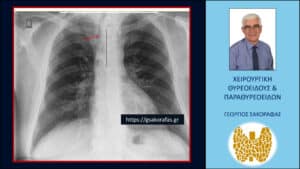

Σημαντική παρεκτόπιση της τραχείας (κόκκινο βέλος) προς τα δεξιά της μέσης γραμμής (μαύρη κάθετη διακεκομμένη γραμμή) από τον διογκωμένο καταδυόμενο αριστερό λοβό του θυρεοειδούς